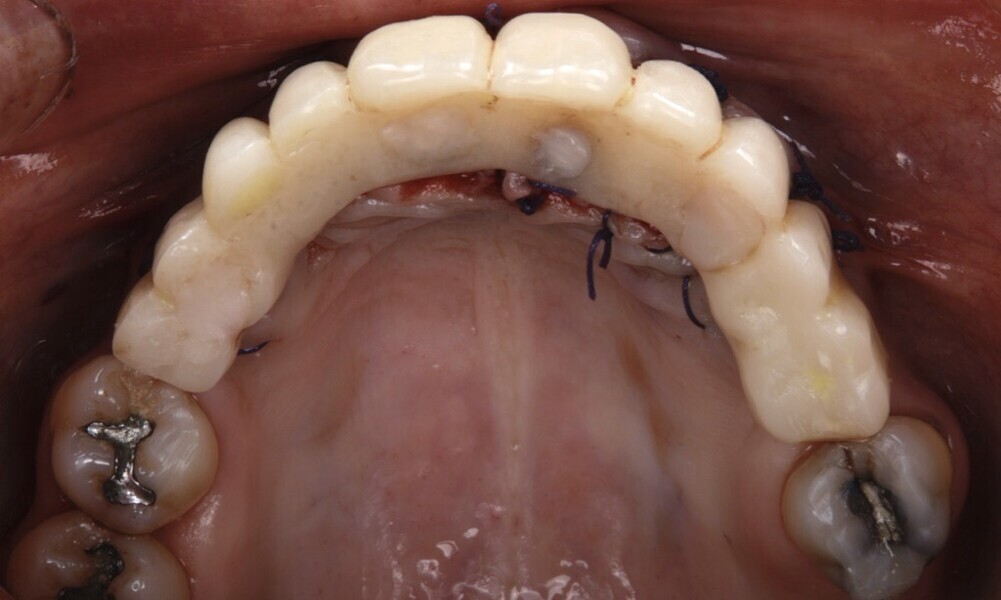

After a healing period of five months and successful osseointegration, the process for the definitive restorations was initiated. The chosen material was milled monolithic zirconia, and Variobase final abutments was used, placed on the screw-retained abutments to ensure excellent stability and retention of the definitive restorations (Figs. 69–75).

Figs. 69–75: The definitive restorations were fabricated after a five-month healing period

The soft tissue was in good condition, and the definitive restorations were placed (Figs. 76 & 77). After placing the definitive restorations, oral hygiene instructions were given to ensure proper care and prevent complications. Additionally, the occlusion was carefully checked and adjusted as needed (Figs. 78–83).

Figs. 76 & 77: Optimal soft tissue conditions were observed, indicating readiness for the definitive restorations.